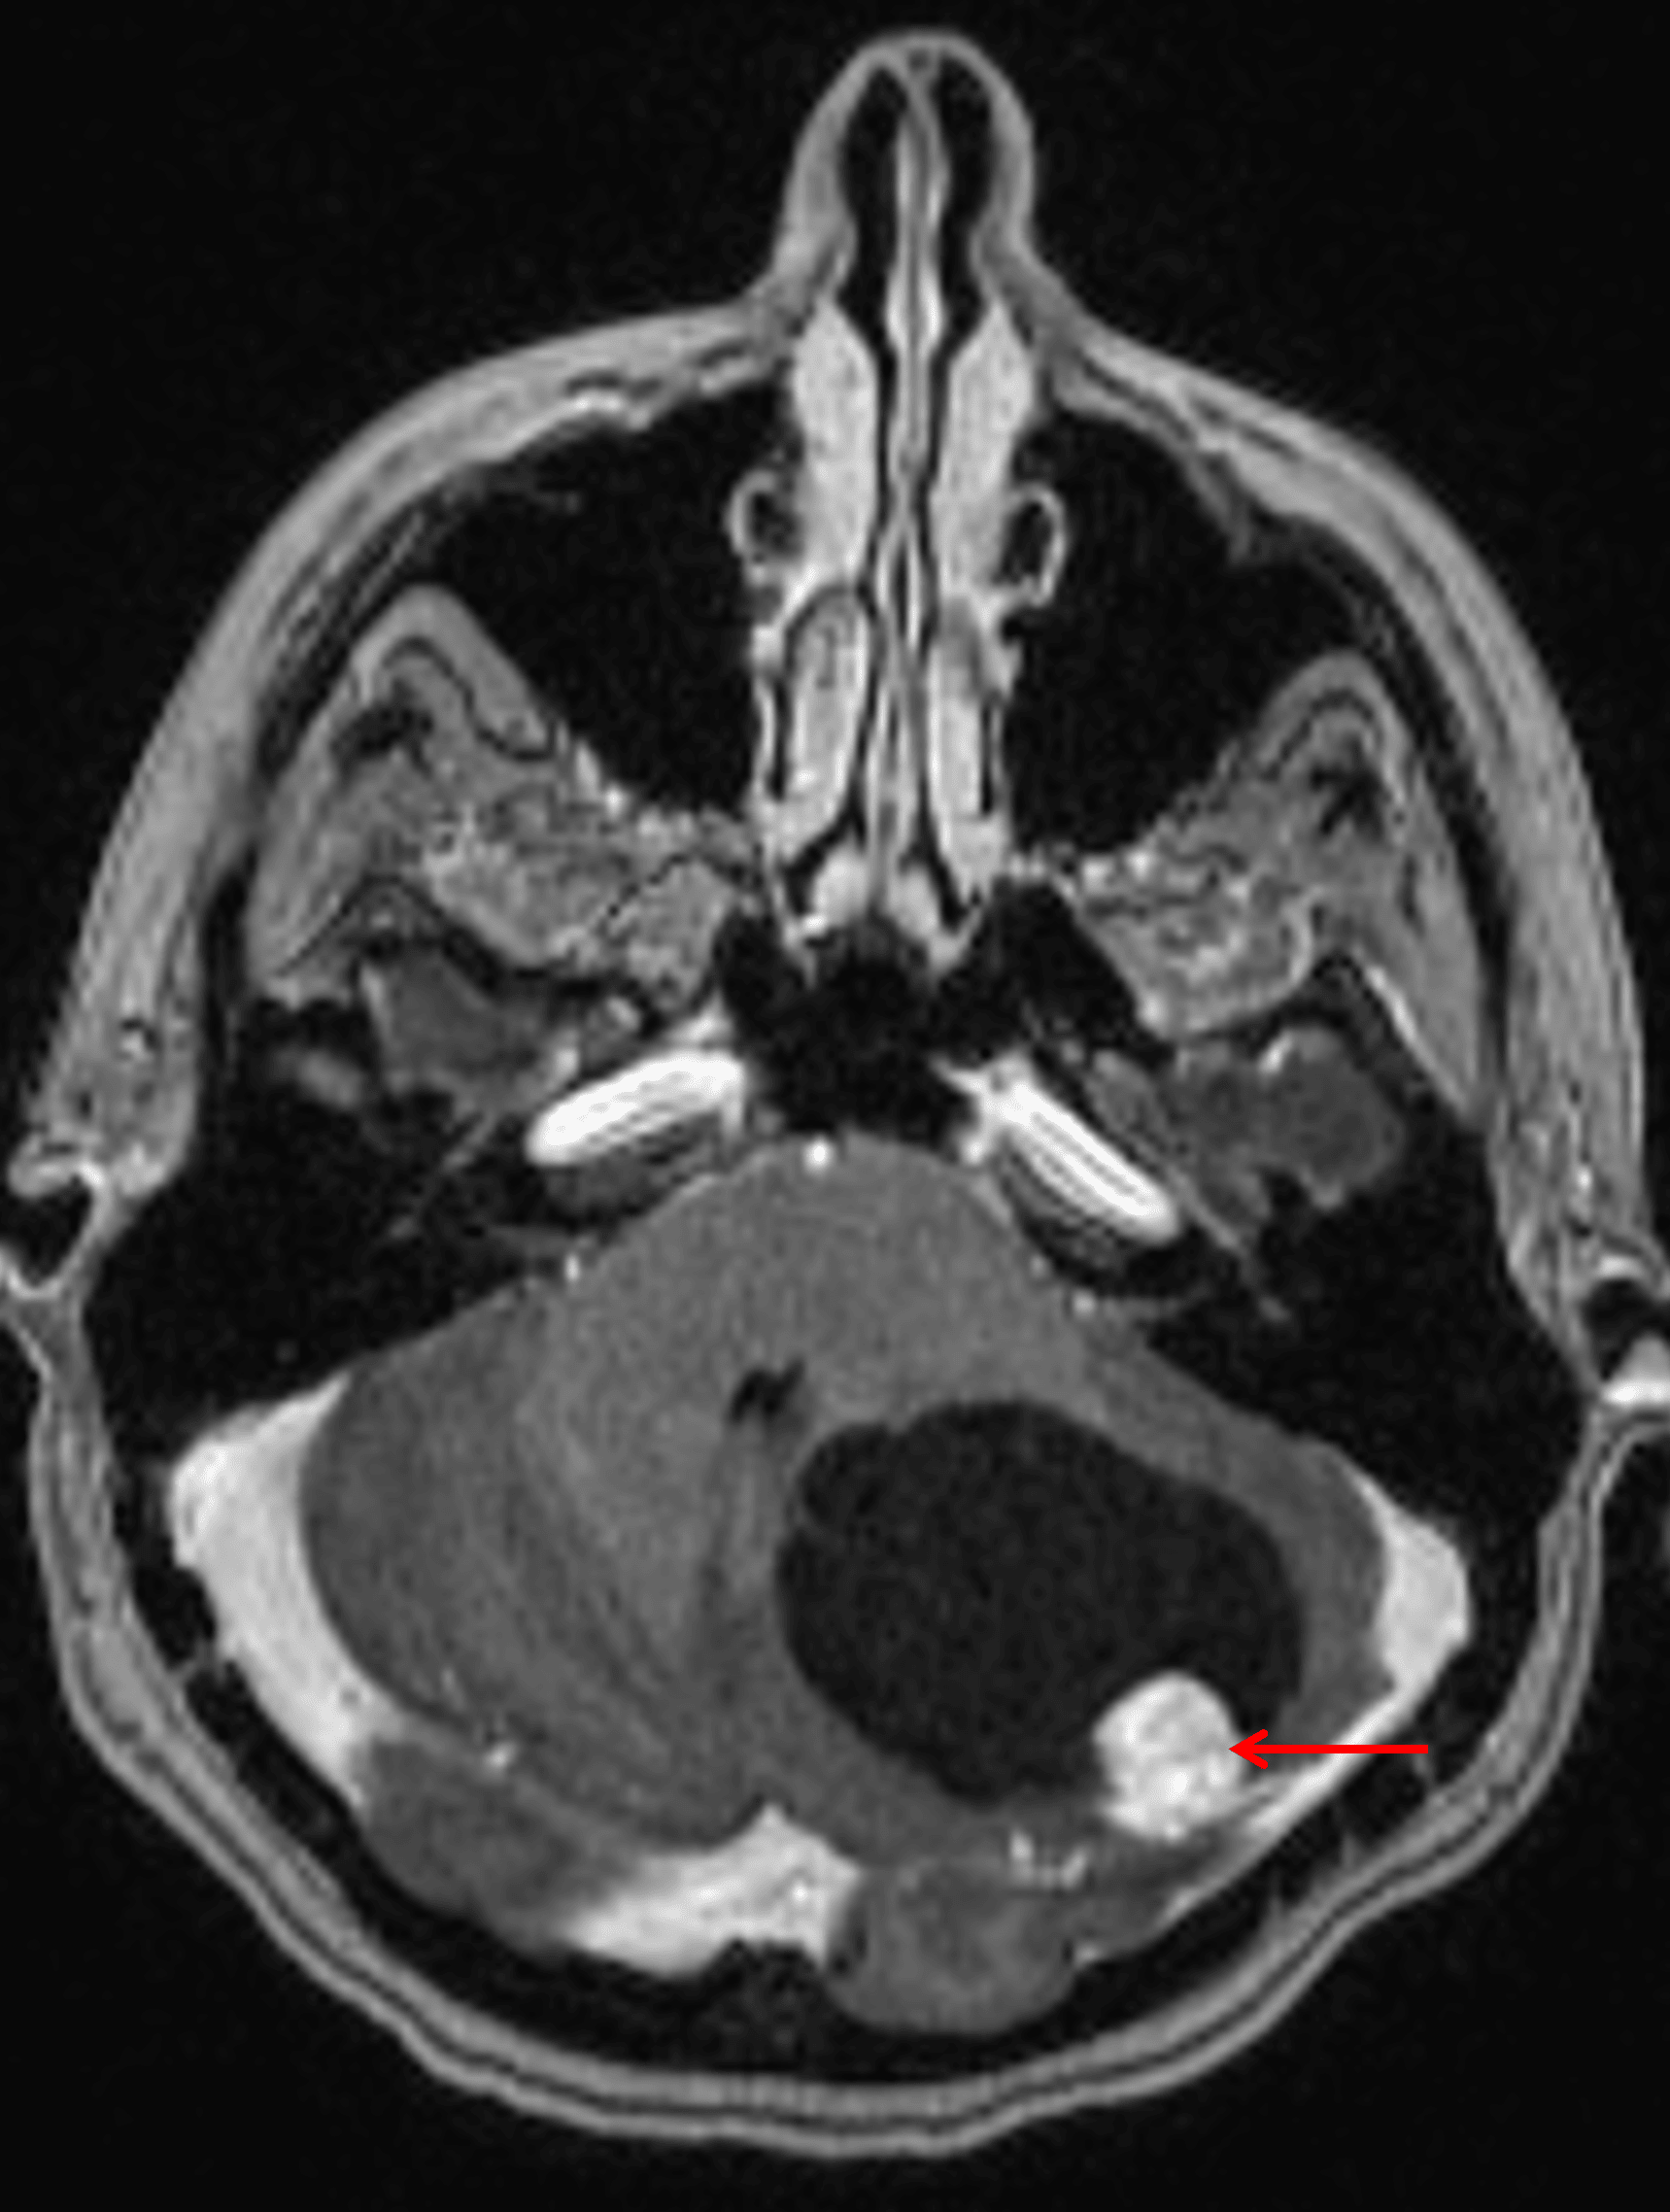

Cystic mass in the left cerebellar hemisphere with an avidly enhancing mural nodule (red arrow).